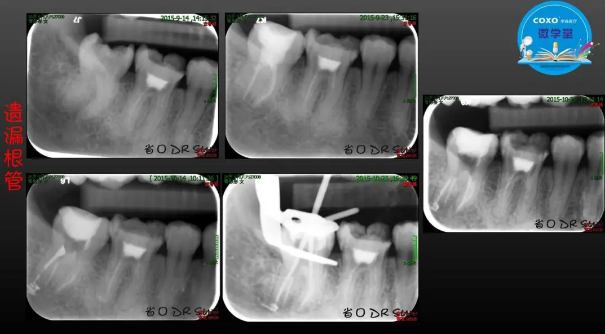

主任醫(yī)師,牙體牙髓副主任, 廣東省口腔醫(yī)院牙體牙髓科 主任醫(yī)師。2003年碩士研究生畢業(yè),研究方向為牙體牙髓病學,擅長于牙體牙髓病的診斷、齲齒、牙髓炎、根尖周病的治療以及前牙美容修復。